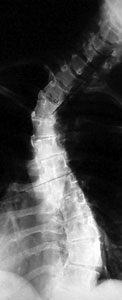

Scoliosis is a disease characterized by an abnormal curvature to the spine, in which the vertebrae twist like a bent corkscrew. In less severe cases, scoliosis may cause the bones to twist slightly, making the hips or ribs appear uneven. When this occurs, the problem is more cosmetic and less of a health risk.

Scoliosis does present a health risk if bones are so severely

twisted that they compress vital organs, or if the spinal deformity is

so severe that spine health and posture is threatened. If this happens,

surgery may be necessary. If left untreated, severe cases of scoliosis

can shorten a person's life span.

- X-rays are usually the first step in diagnostic testing methods. X-rays show bones and the space between bones. They are of limited value, however, since they do not show muscles and ligaments.

Your doctor will take X-rays of your spine which will reveal whether or not scoliosis is present as well as how severe it may be.